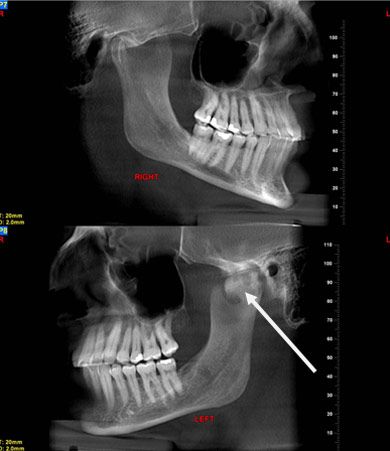

A lateral head/jaw series in the closed and open views (Figure 2) showed a normal jaw opening associated with the abnormality.

Figure 2.